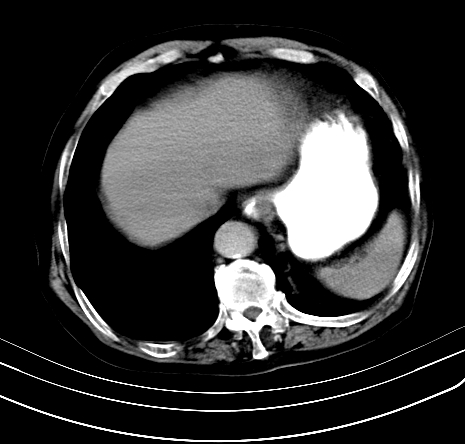

上腹部疼痛不适,行ct检查

胰腺明显肿大,密度减低,考虑慢性胰腺炎,假性囊肿形成不除外。

胰腺明显肿大,考虑慢性胰腺炎假性囊肿形成,不除外胰腺癌可能。

胰腺较明显扩大,胰周有渗出;肾周筋膜有增厚渗出,以左肾为著。应考虑急性胰腺炎。

慢性胰腺炎,假囊肿形成,脂肪肝。